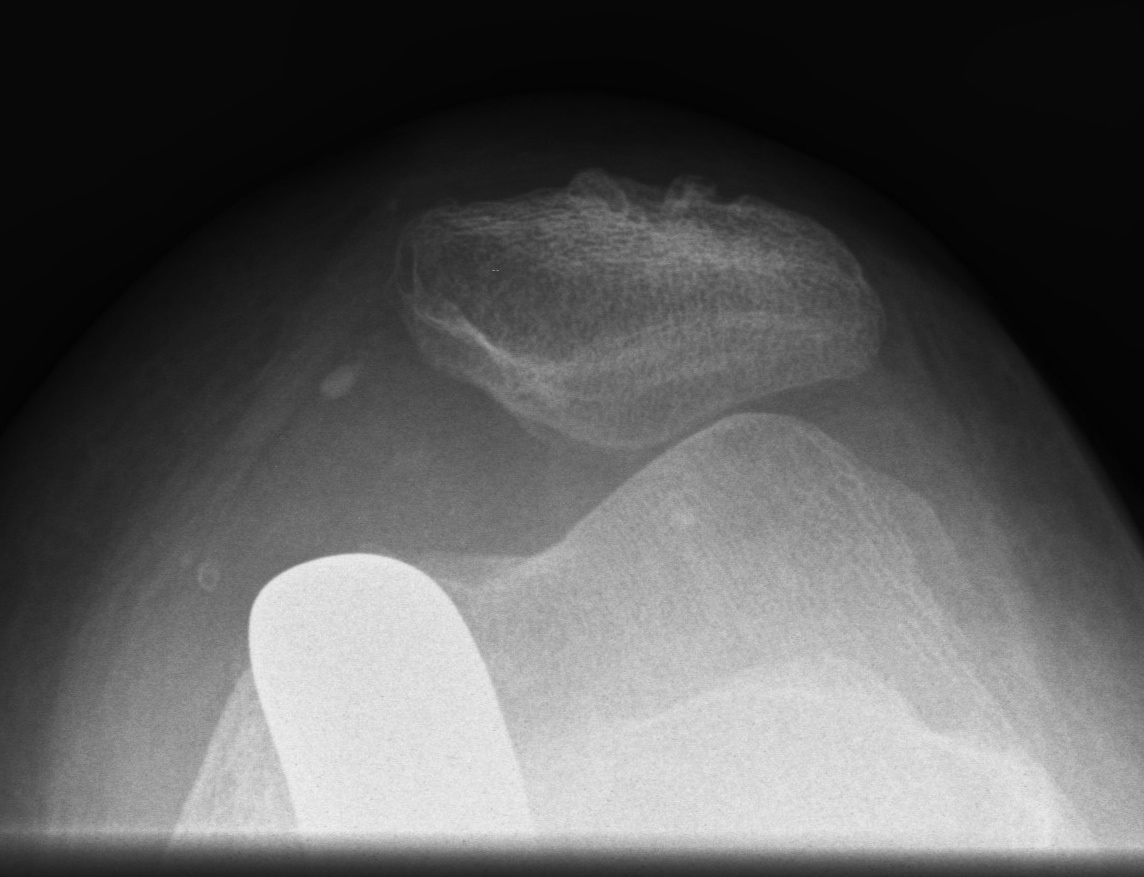

Xray

- skyline views

- lateral tilt / subluxation